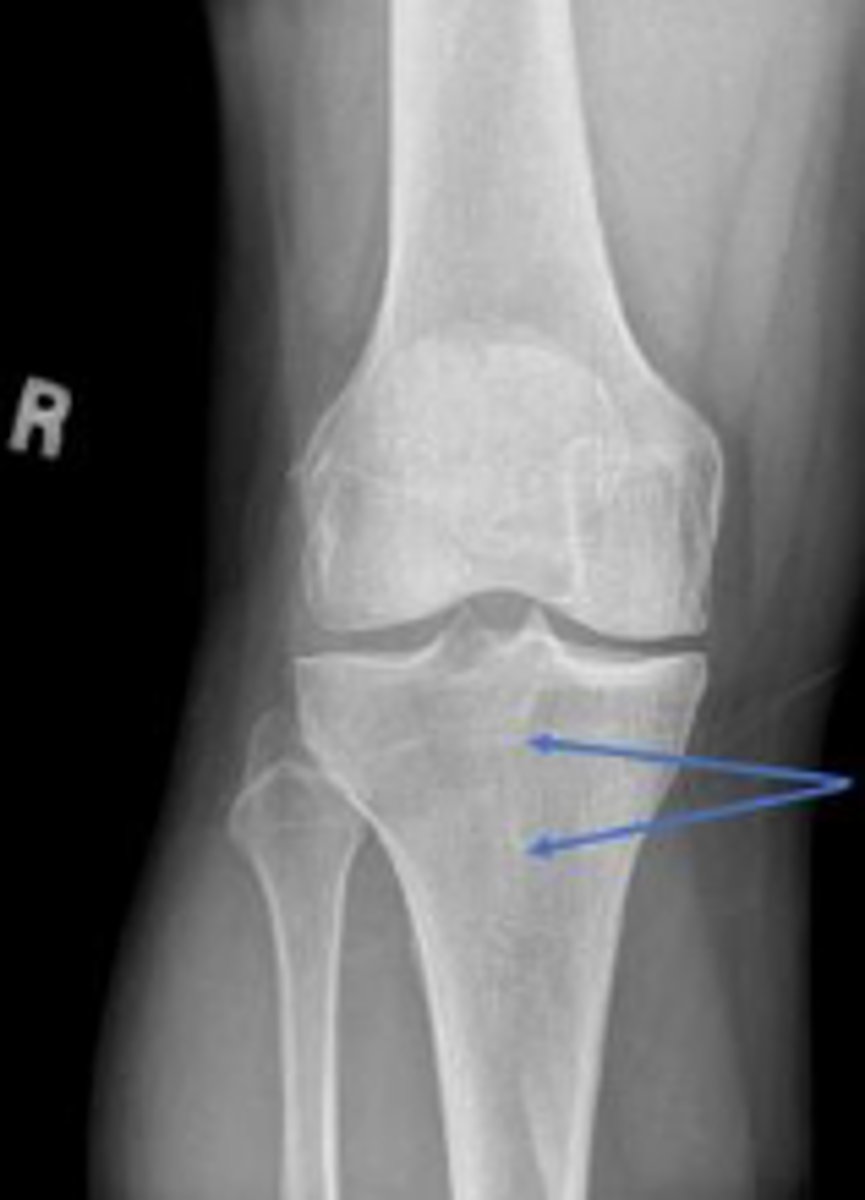

Right proximal tibiofibular joint space

What space are the arrows pointing to?

Lateral collateral ligament

What inserts at the location of the blue arrows?

Lateral collateral ligament avulsion fracture of

the right knee

What is the most significant radiographic finding?